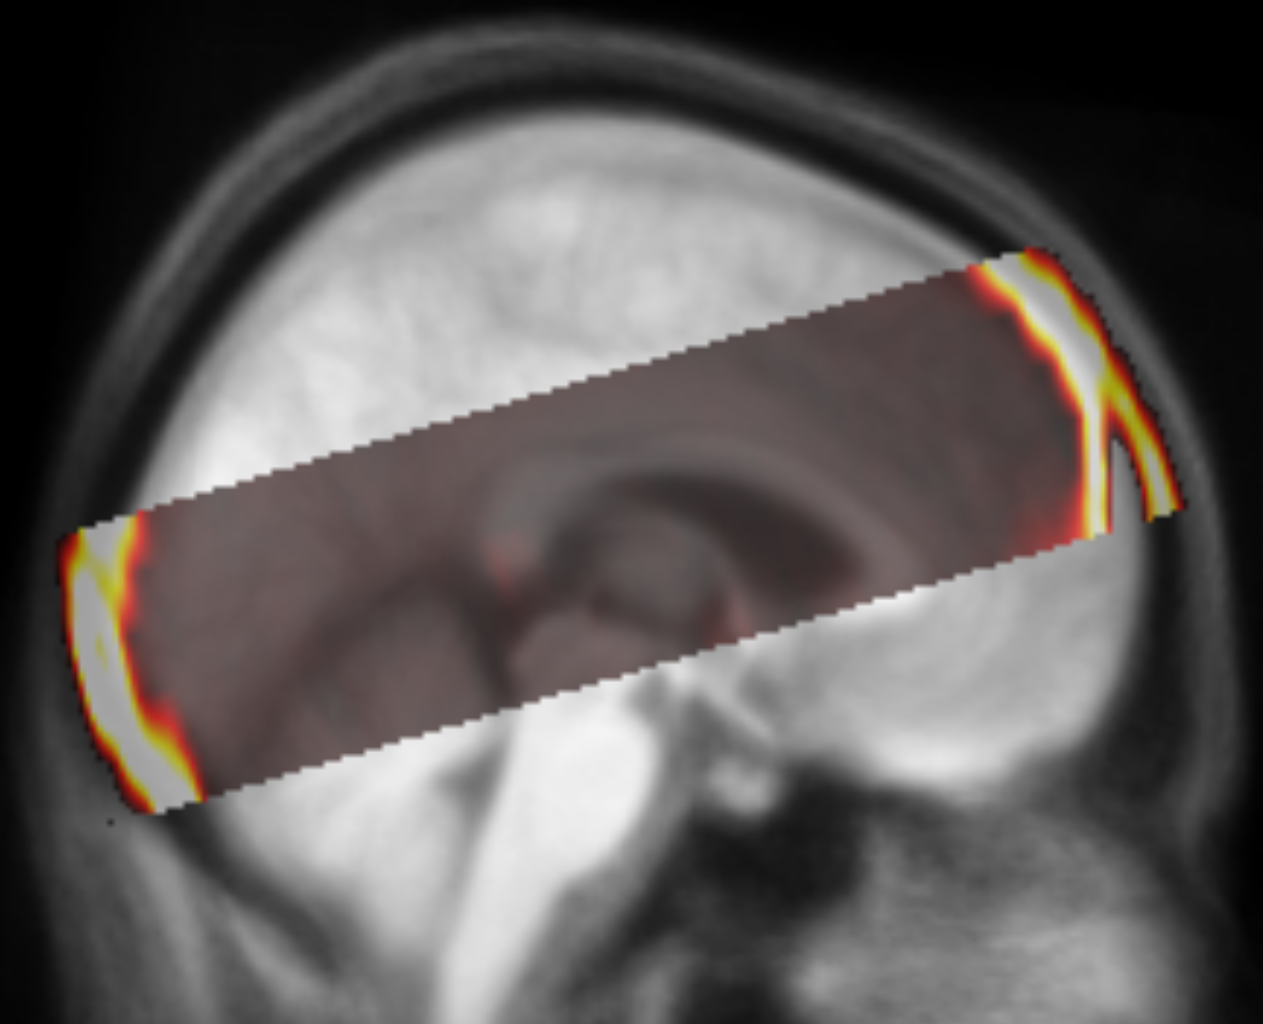

We built custom software to superimpose thresholded ( HU to include calcifications) binary masks derived from the co-registered CT scans to identify anomalies in the alignment with the template and high attenuation values at unexpected locations111https://github.com/bjin96/superimposition-tool. The software provides three views (Figure 2). We use the first view to find anomalies in a large number of CT series. The superimposed image can be inspected in the axial plane and scrolled along the z-axis. Each of the voxels in the view can be selected if any of the binary masks has data at the specific location. If there are multiple binary masks at the selected location (i.e. multiple of the superimposed CT series have values above the threshold at the selected voxel), a single series can be chosen from a list. Upon selection, the alignment of the corresponding binary mask with the MRI template and the original registered series can be examined in the second and third views to inspect the nature of the anomaly and identify possible causes. Found anomalies are documented to a file with a textual comment. The software provides an efficient way to assess a large quantity of registered CT series and find cases with high attenuation values at anomalous locations indicating outliers and inaccurate registrations.